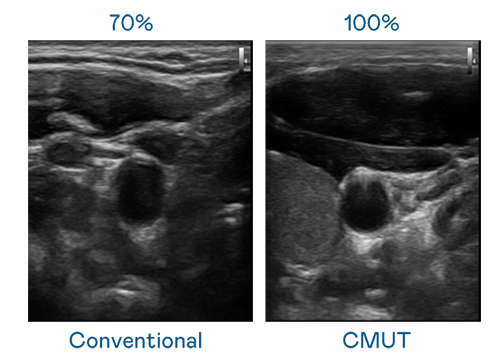

CMUT 技術是一種用電容式微機電元件來產生超音波訊號的技術。與傳統 PZT 壓電式技術相比,CMUT 頻寬增加 30%,更寬頻的超音波訊號讓影像解析度大幅提升,是實現高影像品質醫療超音波掃描、促進精準醫療發展的關鍵技術。

超音波影像的解析度高低,首先取決於探頭能發出的訊號頻寬。PA真人 CMUT 可提供高清晰的超音波訊號,提供高頻寬、高靈敏度、影像紋理細節更高的超音波影像,協助醫護人員縮短影像判讀時間及利用精準的醫療影像進行診斷。